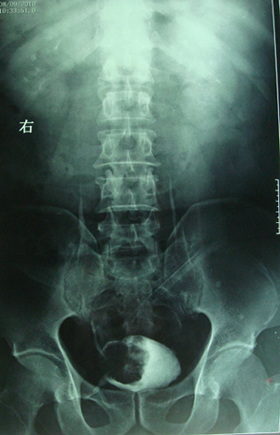

典型病例,男,56岁。无痛性血尿3月。

膀胱占位性病变,呈菜花状生长,考虑膀胱癌。 期待病理。